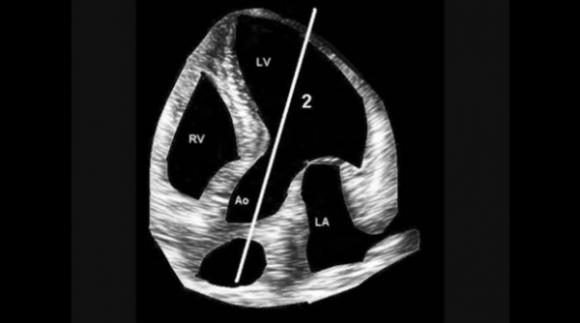

Medico Argentino desarrolla un nuevo método de auscultación cardíaca innovando en el procedimiento luego de 200 años‏

Un nuevo estetoscopio basado en una física distinta del clásico fue desarrollado por un médico argentino. Detecta cosas distintas del ya conocido. Sirve para auscultar el corazón humano y las arterias y venas de...